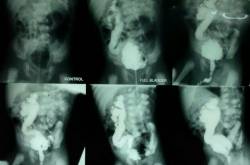

Vesicoureteral reflux (VUR)

Introduction: Vesicoureteral reflux (VUR) represents one of the most significant risk factors for acute pyelonephritis in children Spont......